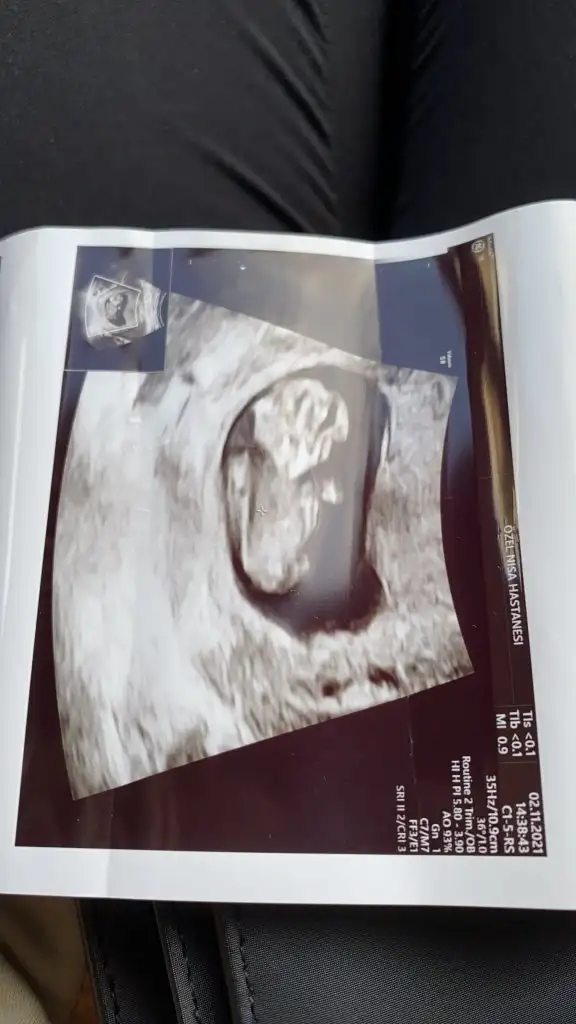

dr soylemeden siz gorun genital nub teorisi ( bebegin cinsiyeti)

Bana da tahmin yurutun ya lutefn 13 haftalık olduk teşekürler şimdiden